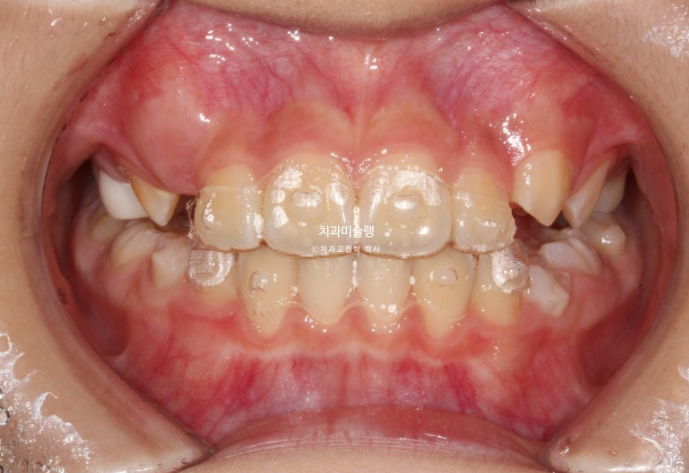

23년 10월 압구정 어린이 교정

교정치료를 위해 온 어린이 입니다.

23.10

윗니가 아랫니를 많이 덮어 아래 앞니가 안 보이는 과개교합이 있습니다.

중심선 불일치도 보입니다.

윗니 뻗침이 있어서 돌출을 느끼는 상태입니다.

앞니 위아래 4개씩 총 8개 영구치 앞니는 약간의 삐뚤함이 있지만 큰 공간부족 없이 잘 나온 편 입니다.